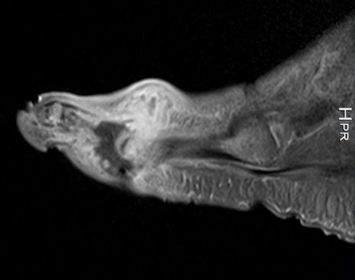

| What does this indicate? | Increased signal and enhancement of the soft tissue plantar to the proximal phalanx suggestive of subcutaneous infection without abscess |

| What does this indicate? | Increased signal and soft tissue distension dorsally representing subcutaneous abscess communicating with associated with plantar ulcerative defect. |